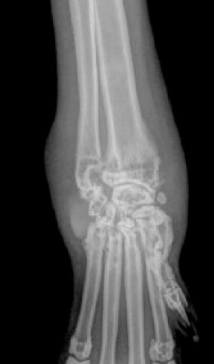

고양이 관절결핵

결핵 하면 폐병 환자, 영화에서 기침하면 손에 맺힌 핏방울을 상상하기 쉽다. 하지만 결핵은 몸 여러 곳에서 병증을 유발할 수 있고 고양이의 경우 관절에서도 발생한다.